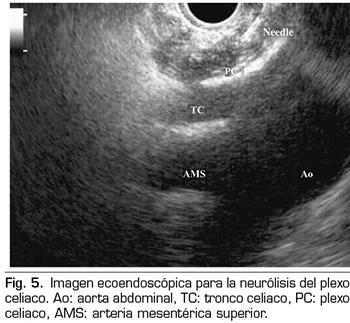

La ecoendoscopia ofrece la ventaja de una mayor visualización del plexo celiaco a corta proximidad, permitiendo una mayor precisión y seguridad en la administración del agente neurolítico y evitando la inyección en estructuras vasculares mediante el uso del Doppler (37) (Figura 5). No obstante, los trabajos que apoyan la neurólisis ecoendoscópica, considerada al igual que la técnica percutánea como una terapia de rescate, están limitados a estudios retrospectivos no controlados (38). Pauli y cols. publicaron un metanálisis que concluye que esta técnica consigue una reducción del dolor del 80 % en pacientes con cáncer de páncreas (39). Algunos estudios muestran un ligero descenso en el consumo de opioides, pero sin una fuerte evidencia científica.

En cuanto a los efectos adversos, se limitan a una serie de publicaciones retrospectivas y series de casos, estando descritos la hipotensión (11 %), la diarrea (18 %) y el dolor abdominal transitorio (1,5 a 8 %) (37). Teóricamente, esta técnica es más segura, con su abordaje anterior a través de la pared gástrica y paso directo de la aguja al plexo visualizando los vasos, sin tener que atravesar el espacio retrocrural (41). Aun así, también se han publicado complicaciones fatales con esta técnica. Gimeno-García y cols. (42) describieron la primera complicación de trombosis y vasoespasmo de la arteria celiaca que produjo una isquemia multiorgánica y la muerte del paciente. Desde entonces esta complicación se ha publicado en otros 2 trabajos, que también acabaron en muerte (43,44). Otros efectos adversos descritos son el sangrado retroperitoneal y 2 casos de paraplejia.

Dentro de las contraindicaciones relativas a esta técnica se encuentran: la presencia de varices gástricas o esofágicas −ya que aumentan el riesgo de sangrado−, una anatomía desestructurada, la invasión tumoral directa del plexo, y las malformaciones congénitas del tronco celiaco o de la arteria mesentérica superior.